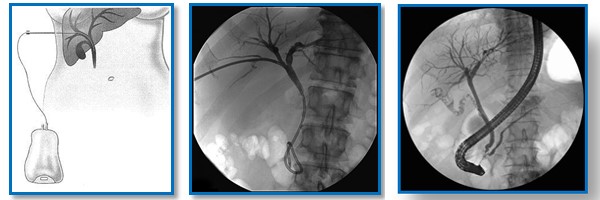

- تصوير الأقنية الصفراوية بالتنظير الباطني، ويكون عن طريق إدخال أنبوب رفيع مرن عبر حلق المريض ومنه إلى المعدة وللأمعاء الدقيقة، وبمساعدة الصبغة يستطيع الطبيب رؤية المرارة بدقة.